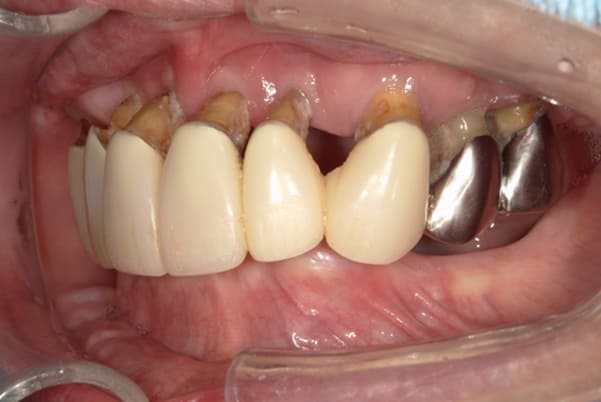

下顎治療前

-

下顎治療後

治療前の入れ歯の奥歯は、治療後の義歯と比較しても分かるように、歯が削れ平らになった状態です。

これにより奥歯のかみ合わせは低くなり、前歯のみが強くあたり、かみ合わせにより上の前歯大きな負担がかかっていたことにより、上の前歯が折れたことが考えられます。